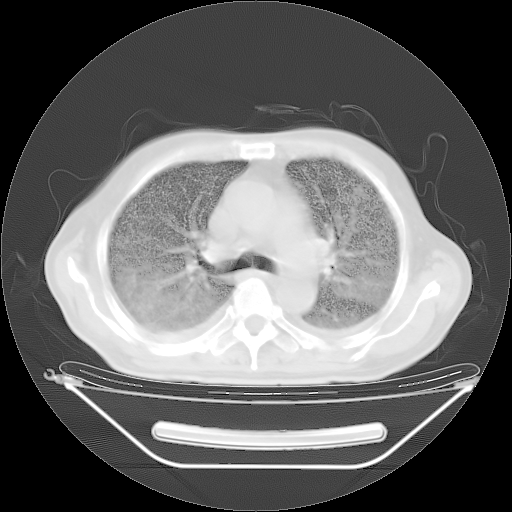

胸腹部CT,诊断意见:左上肺叶钙化灶、左侧胸膜局限性增厚并钙化、胆囊炎。描述部分肺组织呈磨玻璃样改变。